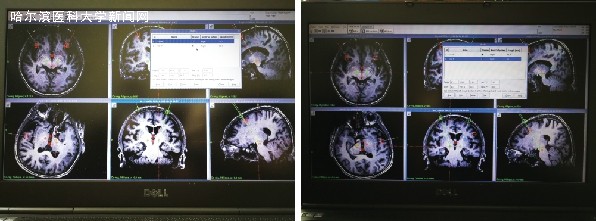

术前进行手术规划

术中测试,微电极记录到核团细胞放电,意味着电极成功植入到脑深部核团的预定目标

经过严格的术前评估和讨论,决定采用DBS。术中采用局麻+全身麻醉方法,郭冕在局麻下颅骨钻孔,立体定向引导下顺利植入双侧电极,实现了准确无误地将电极植入到脑深部核团的预定目标并在术中测试成功控制症状;接着在全麻下将脉冲发生器埋入胸前皮下,通过连接线连接电极和脉冲发生器,整个手术过程非常顺利。术后一个月开机程控,调节好程控参数后,张女士身体震颤僵直的情况立即改善,时隔五年可以再一次独自行走的张女士,流下了激动的泪水。